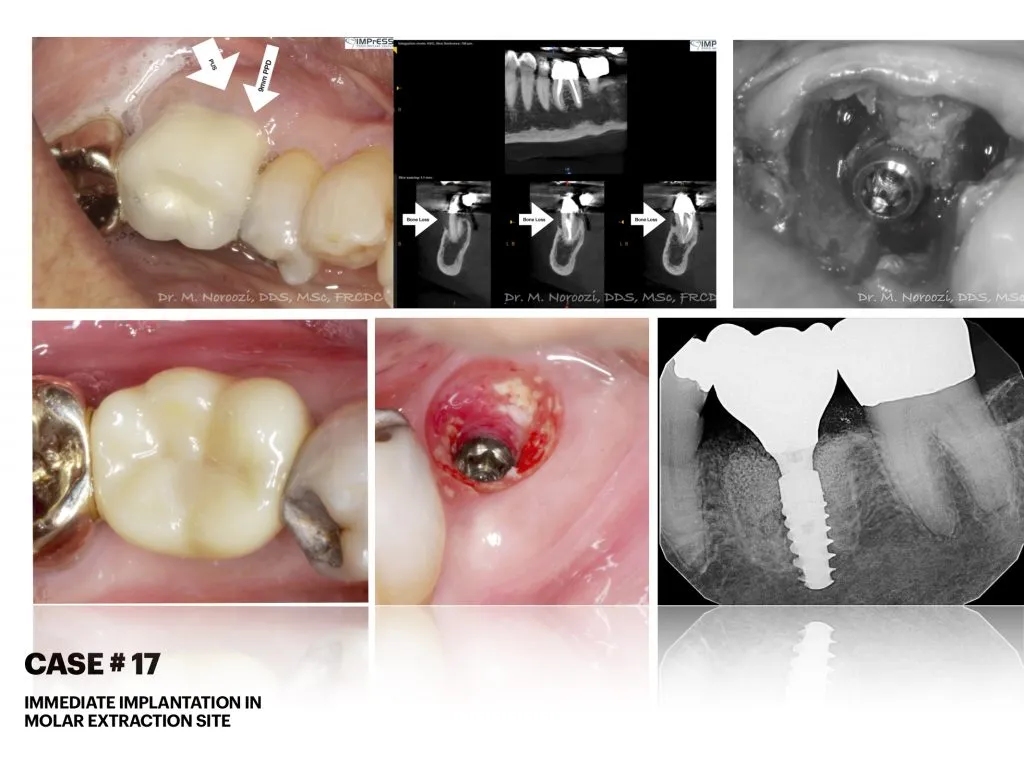

Before & Afters of Dental Implant Patients

Complete Dental Implant Cases Gallery

Surgical advances with SAME-DAY IMPLANTS in Vancouver BC

Using the most recent advances in dental implant technology, Dr. Noroozi is able to place single stage implants. These implants do not require a second procedure to uncover them but may require a minimum of six weeks of healing time before artificial teeth are placed. There are even situations where the implant can be placed at the same time as the tooth extraction and the artificial tooth can be inserted immediately following the implant placement – further minimizing your number of surgical procedures.

General Disclaimer: The results in the photographs are examples only and do not imply any certainty of the result of a procedure, and all outcomes are subject to the circumstances of the individual patient.